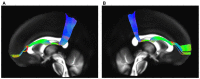

The existence of the superior fronto-occipital fasciculus (SFOF) in the human brain remains controversial. The aim of the present study was to clarify the existence, course, and terminations of the SFOF. High angular diffusion spectrum imaging (DSI) analysis was performed on six healthy adults and on a template of 842 subjects from the Human Connectome Project. To verify tractography results, we performed fiber microdissections of four post-mortem human brains. Based on DSI tractography, we reconstructed the SFOF in the subjects and the template from the Human Connectome Project that originated from the rostral and medial parts of the superior and middle frontal gyri. By tractography, we found that the fibers formed a compact fascicle at the level of the anterior horn of the lateral ventricle coursing above the head of caudate nucleus, medial to the corona radiate and under the corpus callosum (CC), and terminated at the parietal region via the lower part of the caudate nucleus. We consider that this fiber bundle observed by tractography is the SFOF, although it terminates mainly at the parietal region, rather than occipital lobe. By contrast, we were unable to identify a fiber bundle corresponding to the SFOF in our fiber dissection study. Although we did not provide definite evidence of the SFOF in the human brain, these findings may be useful for future studies in this field.